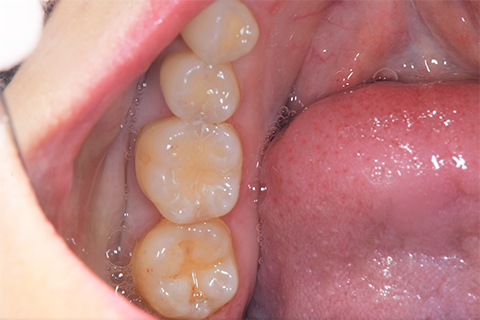

インレーの症例

インレー症例

治療前

途中経過

治療後

年齢・性別 43代・女性

主訴 パラジウムインレー2次カリエスの治療

治療内容 左上6セラミックインレー・

左上7ゴールドインレー

治療期間 10日程度

リスク・副作用 虫歯が深ければ、つけた後しみたり、痛みが出る可能性がある。 その場合は神経をとる処置をする。

歯ぎしり、くいしばりでセラミックインレーが割れることがある。

費用 セラミックインレー 55,000円

ゴールドインレー 88,000円